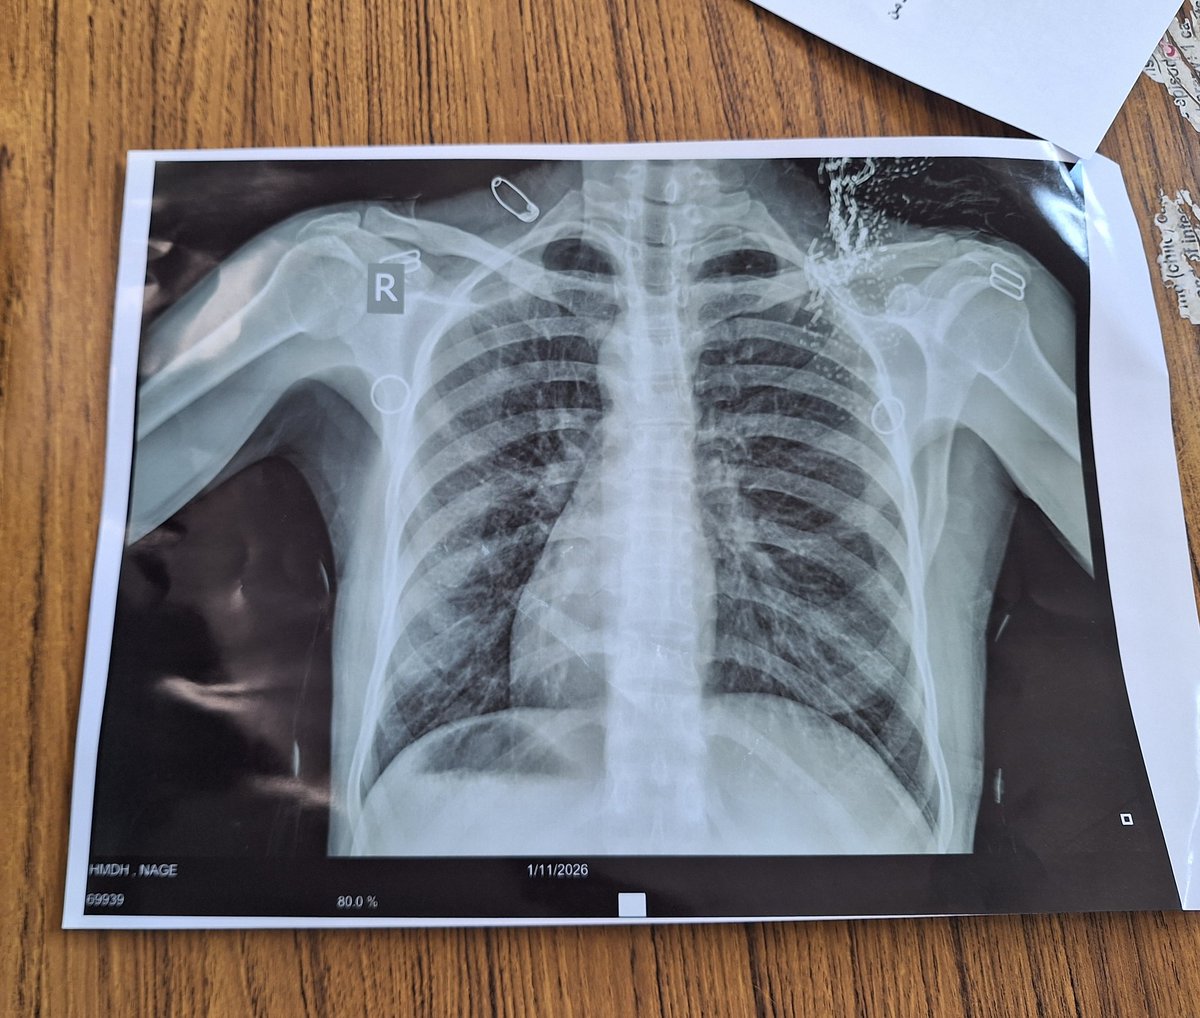

@kh505043 situs inversus لان القلب لليمين و الgastric bubble على اليمين

Dr. Khaled@kh505043·

بعيداً عن امراض الجهاز التنفسي في شي غريب في الأشعة اكتشفناه اليوم في عيادة الصدر لمريض خمسينيه... يا ترى ايش ممكن يكون ؟؟؟!🤔🤔